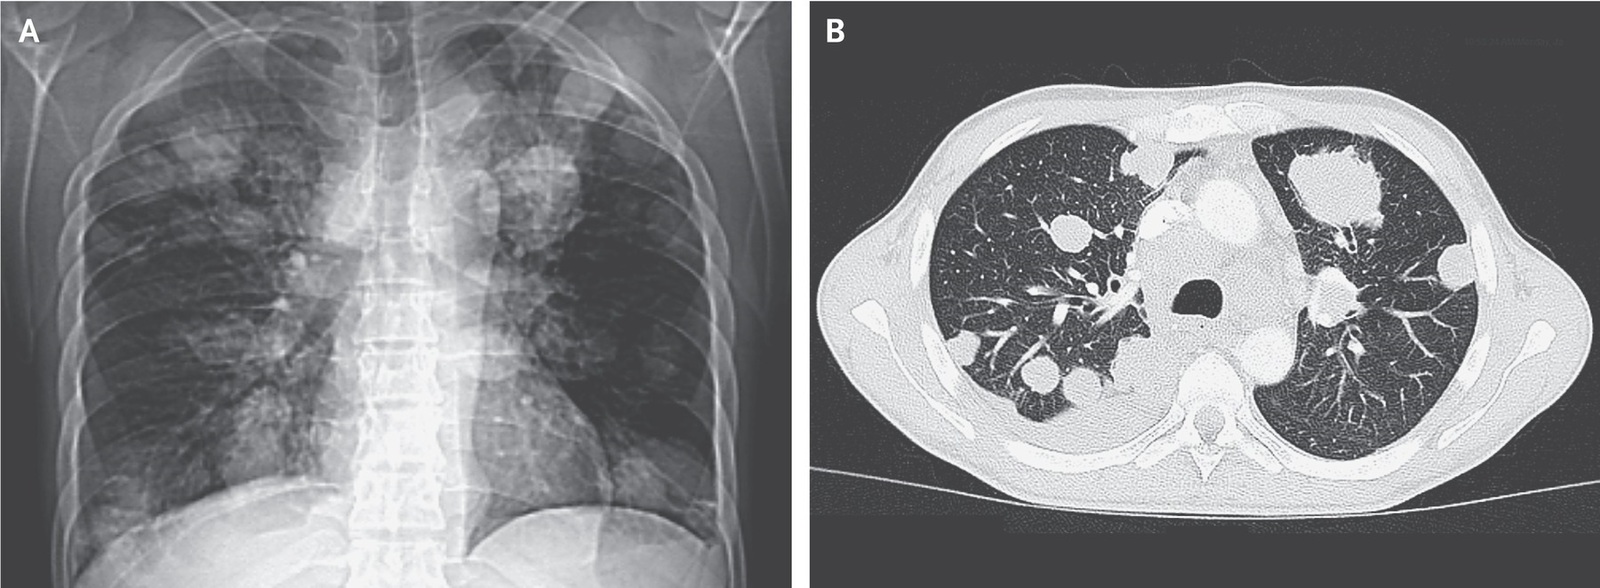

МСКТ показало наличие очагового поражения легких и печени, а также увеличение шейных, медиастинальных и абдоминальных лимфузлов.